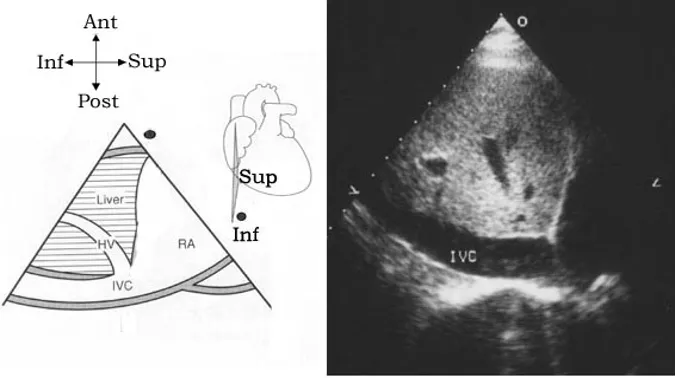

剑突下上下腔长轴切面